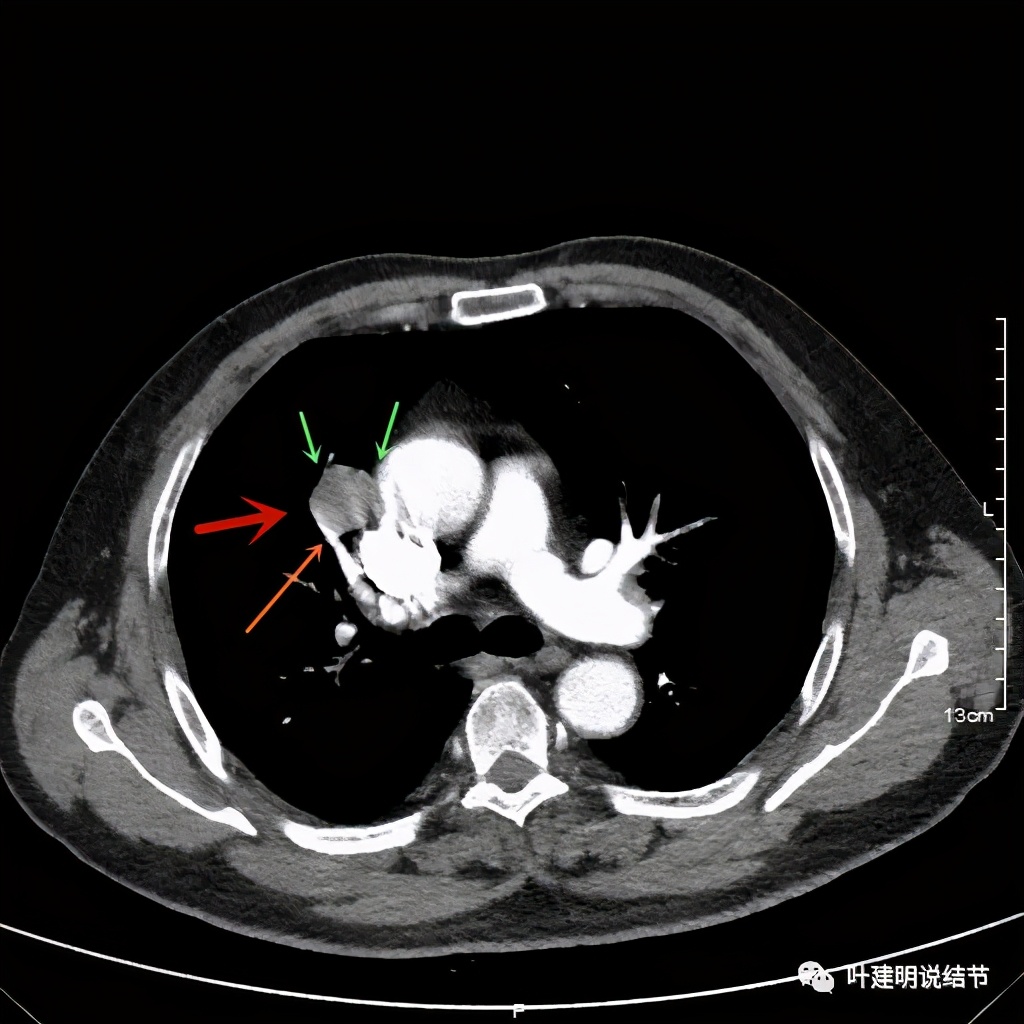

上图示病灶边缘过于光滑(绿色);血管贴边(桔色);

上图示病灶边缘过于光滑(绿色);血管贴边走行(桔色)

以上几图也示病灶边缘过光(绿色);血管贴边,感觉没受侵犯(桔色)